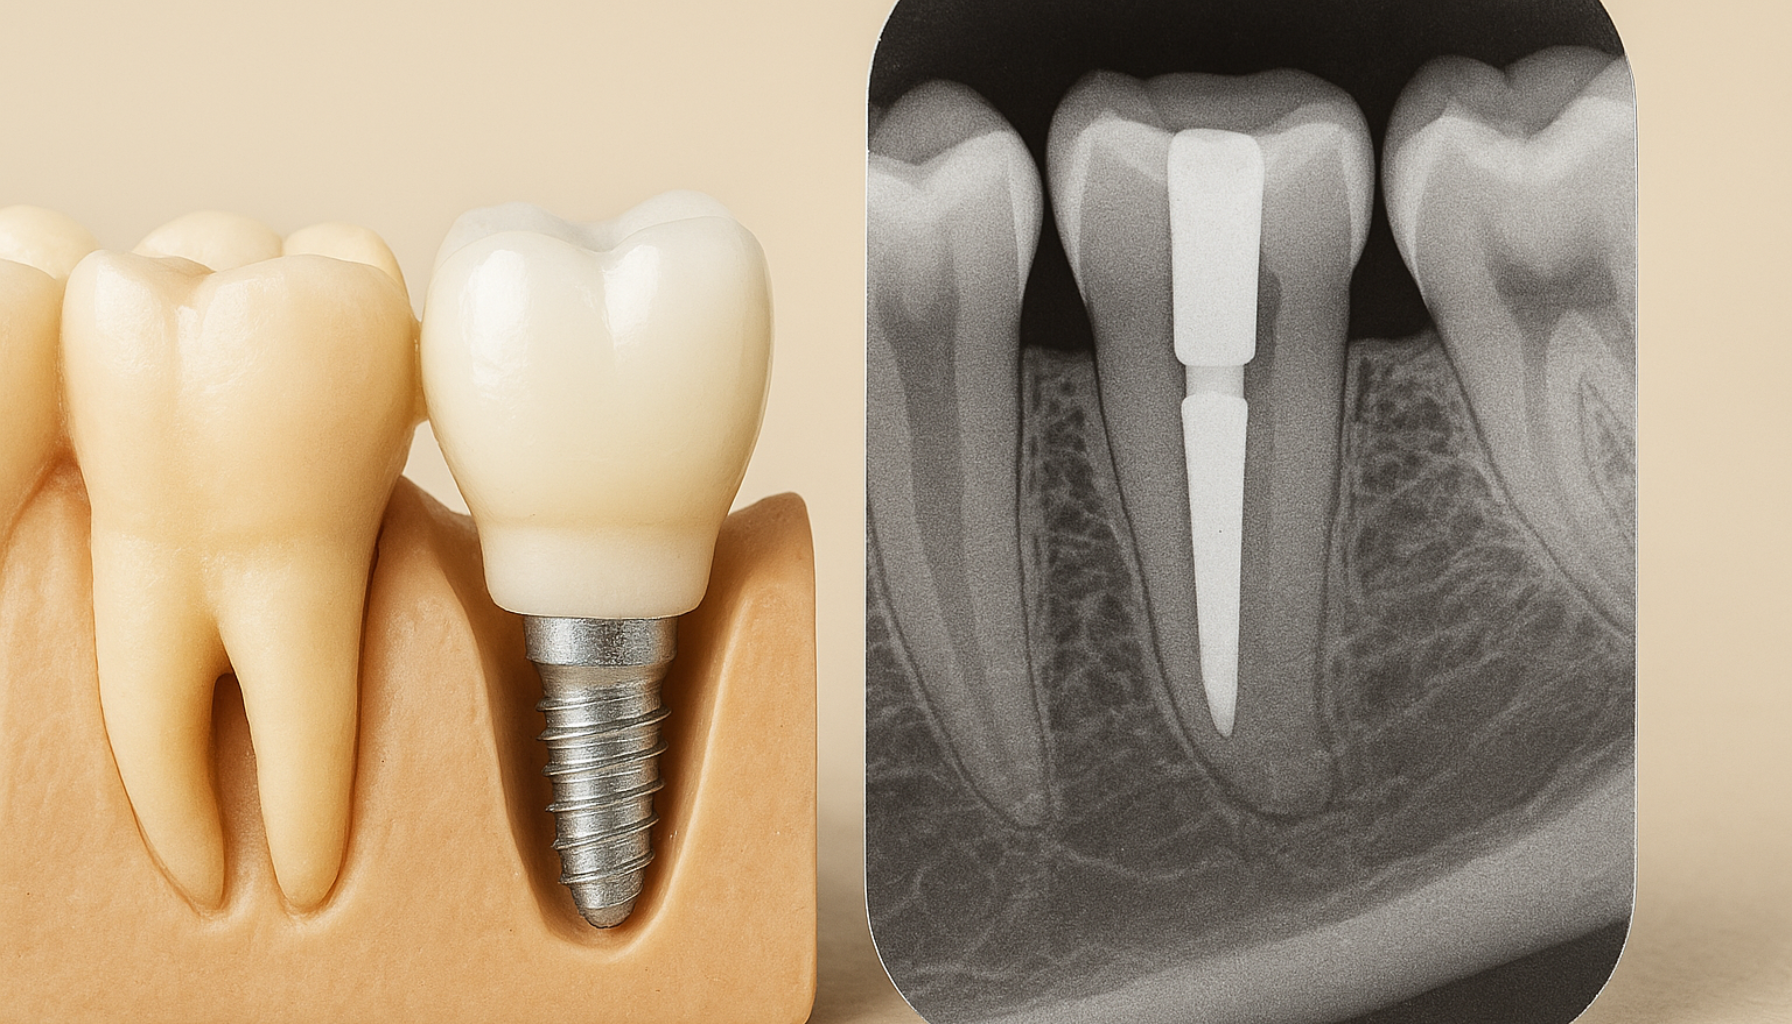

Prosedyren for å sette en tann på stift skjer i flere trinn. Først vil tannlegen gjøre en grundig vurdering av tannen for å sikre at den er egnet for behandling. Dette kan innebære røntgenbilder for å vurdere rotens tilstand. Deretter vil tannlegen fjerne eventuelle rester av infisert eller dødt vev i rotkanalen, før de fyller den med et spesialmateriale som tetter kanalen.

Når rotkanalen er forberedt, plasseres en stift, som vanligvis er laget av metall eller fiber, inn i rotkanalen. Denne stiften fungerer som et fundament for kronen. Etter at stiften er på plass, formes og justeres tannen for å gjøre plass til kronen. Kronen, som kan være laget av porselen, keramikk eller metall, plasseres deretter over stiften for å gi tannen en naturlig form og styrke.

Før stiften kan settes inn, må tannen være rotfylt. Det er viktig at rotfyllingen er tett og stabil for at behandlingen skal lykkes. - Slik fungerer stiften:

Stiften plasseres i rotkanalen og fungerer som et indre skjelett. Deretter bygges det opp en kjerne og til slutt en krone over – noe som gir god styrke og støtte. - Stift og krone i ett system: